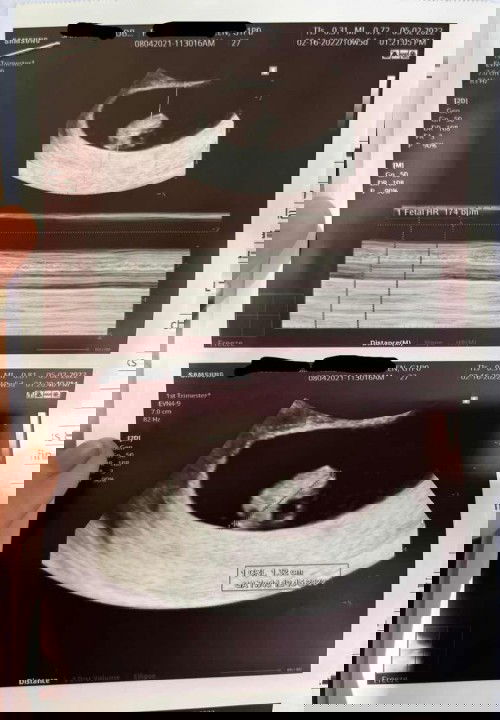

First ultrasound

Thank you Lord sa beautiful blessing! πŸ˜‡πŸ₯° So greatful! 7 weeks 4 days based sa ultrasound. May heartbeat na si baby πŸ’— Excited na si Mommy and Daddy makita ka anak πŸ€— #firsttiimemom